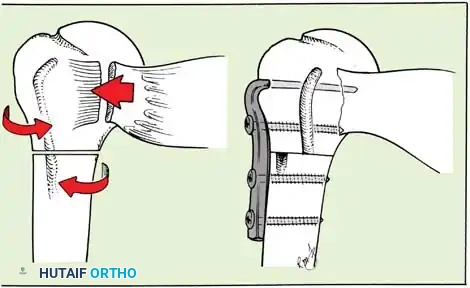

Exposure of the anterior capsule requires navigating the subscapularis muscle. Historically, a vertical tenotomy was performed; however, modern techniques favor a subscapularis split or a peel to preserve the integrity of the muscle belly and its tendinous insertion.

- The Split: A horizontal split is made in the subscapularis at the junction of its middle and inferior thirds, extending from the lesser tuberosity medially.

- Separation: The subscapularis is carefully elevated off the underlying anterior joint capsule. This plane can be scarred in revision cases, requiring meticulous sharp dissection to avoid inadvertent capsulotomy.

Capsular Shift and Closure

To address capsular redundancy, an inferior capsular shift is performed.

- The arm is positioned in 30 to 45 degrees of abduction and 20 degrees of external rotation.

- The inferior capsular flap is advanced superiorly and laterally, tensioning the IGHL complex. The sutures from the anchors are passed through the shifted capsule and tied.

- The superior flap is then brought down over the inferior flap in a "pants-over-vest" fashion to reinforce the anterior wall and close the rotator interval.

- The subscapularis split is loosely approximated with absorbable sutures. The deltopectoral interval is closed over a suction drain (if necessary), followed by routine subcutaneous and skin closure.